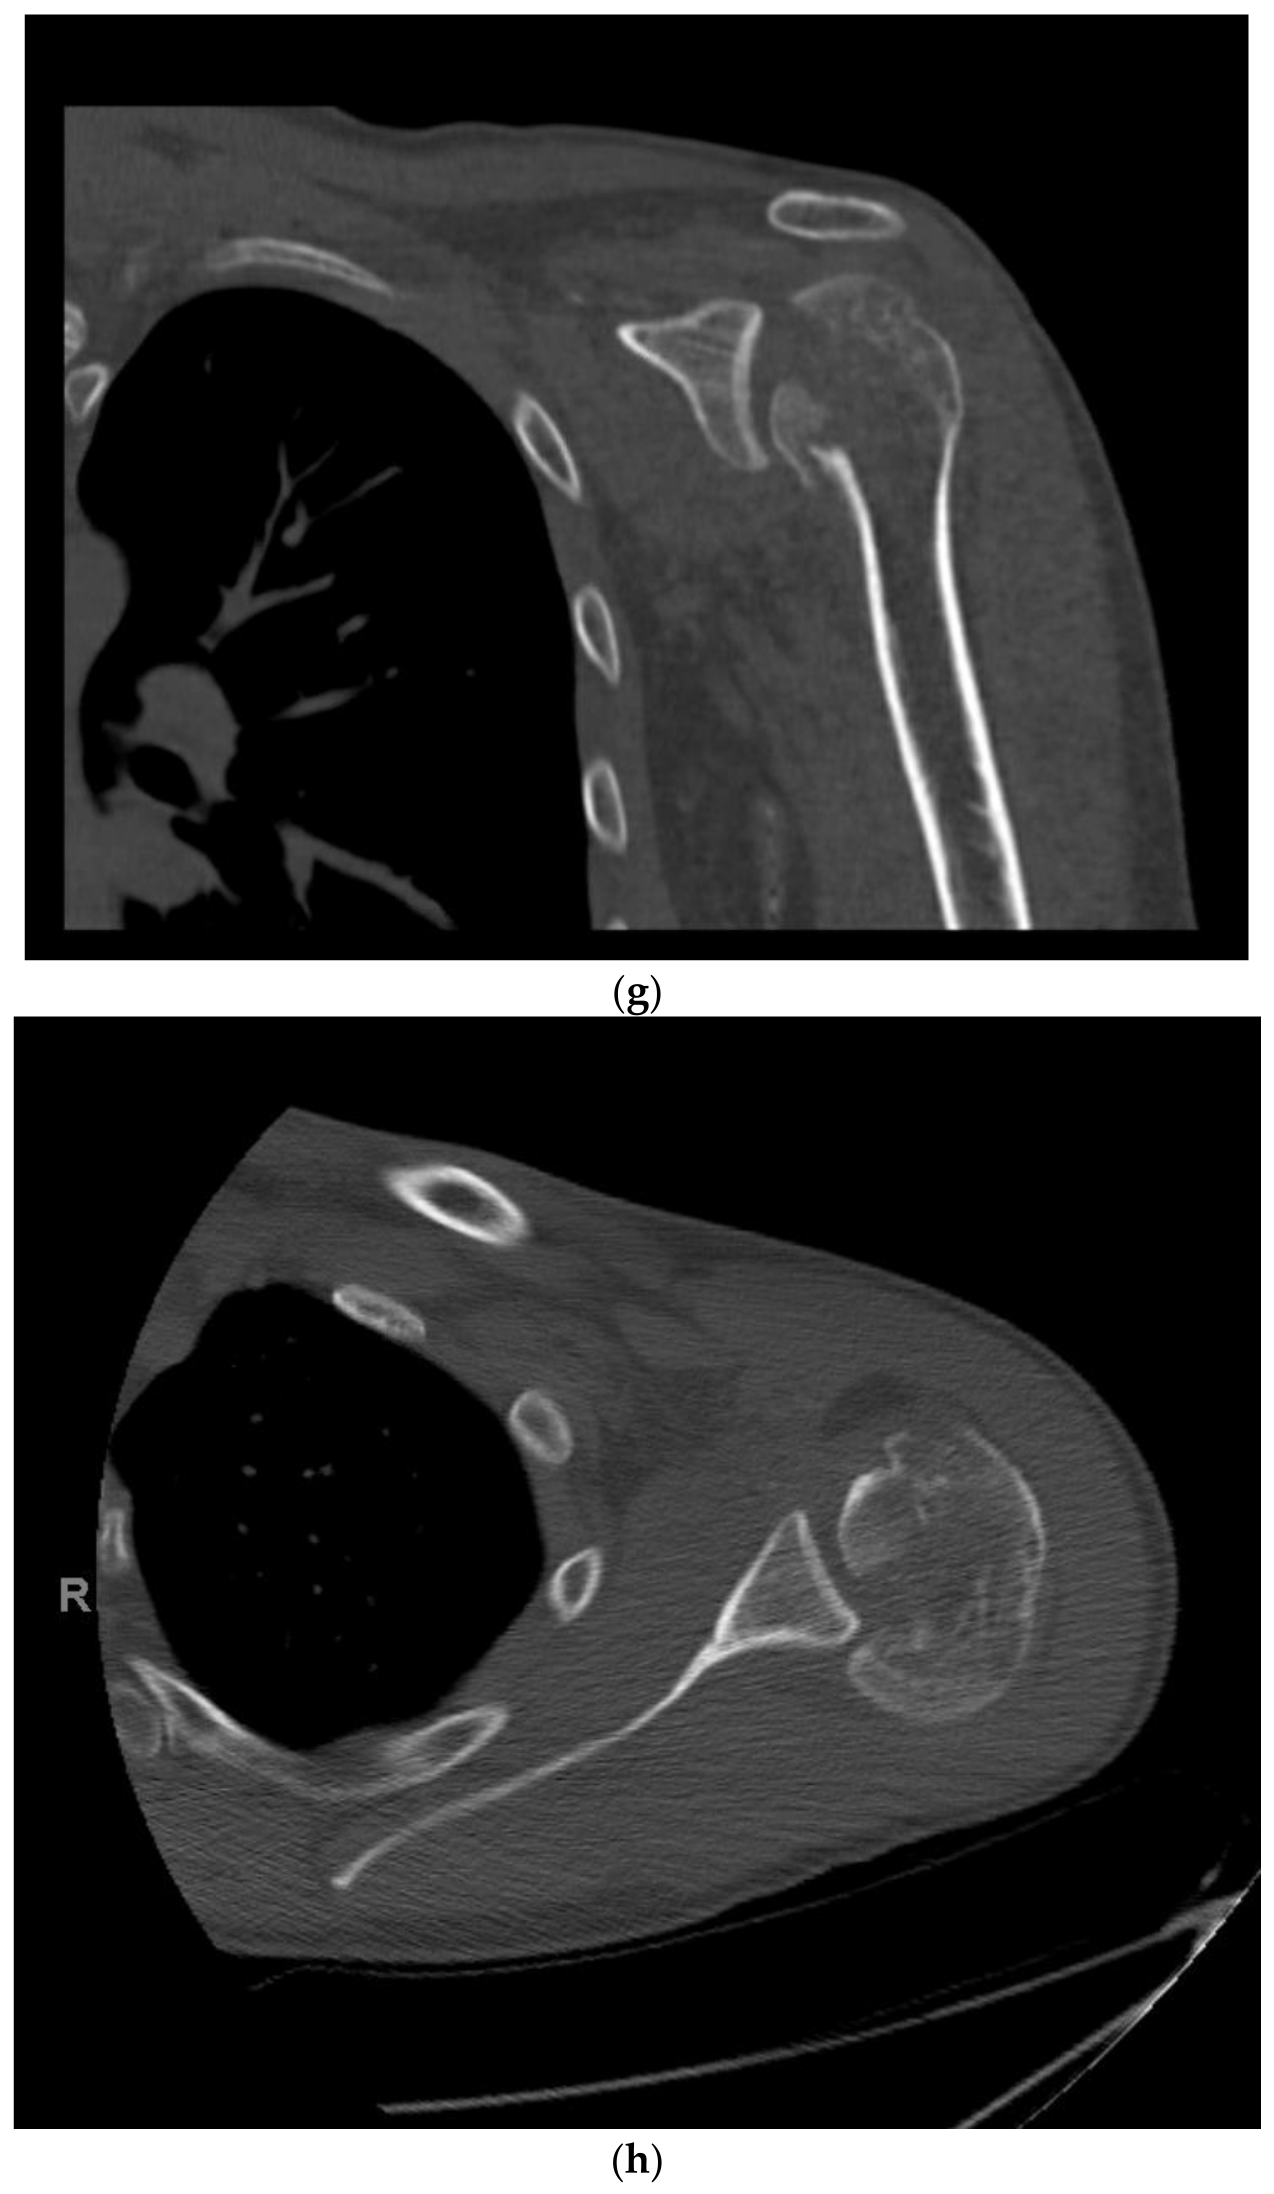

15. Hemiarthroplasty

15.1. Patient Positioning

15.2. Surgical Approach

15.3. Postoperative Management

15.4. Complications

15.5. Outcomes